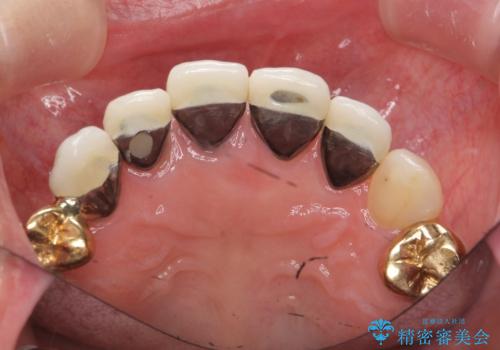

視診・X線写真検査より根尖性歯周炎が認められ再治療が必要な状態です。

再根管治療を行うべくクラウン除去を行ったところ、右上側切歯に保存不可能な垂直性の破折が認められたため抜去が必要になりました。

即切歯の抜歯を行う場合犬歯を含めたブリッジによる補綴計画を立てることが多いですが、今回は犬歯から大臼歯にかかる大きなブリッジが既に装着されていたため予算とご希望を相談し前歯のみの延長ブリッジ補綴で治療を行っていくこととしました。